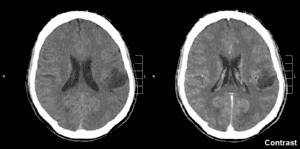

| Glioma in the left parietal lobe (brain CT scan), WHO grade 2. | |